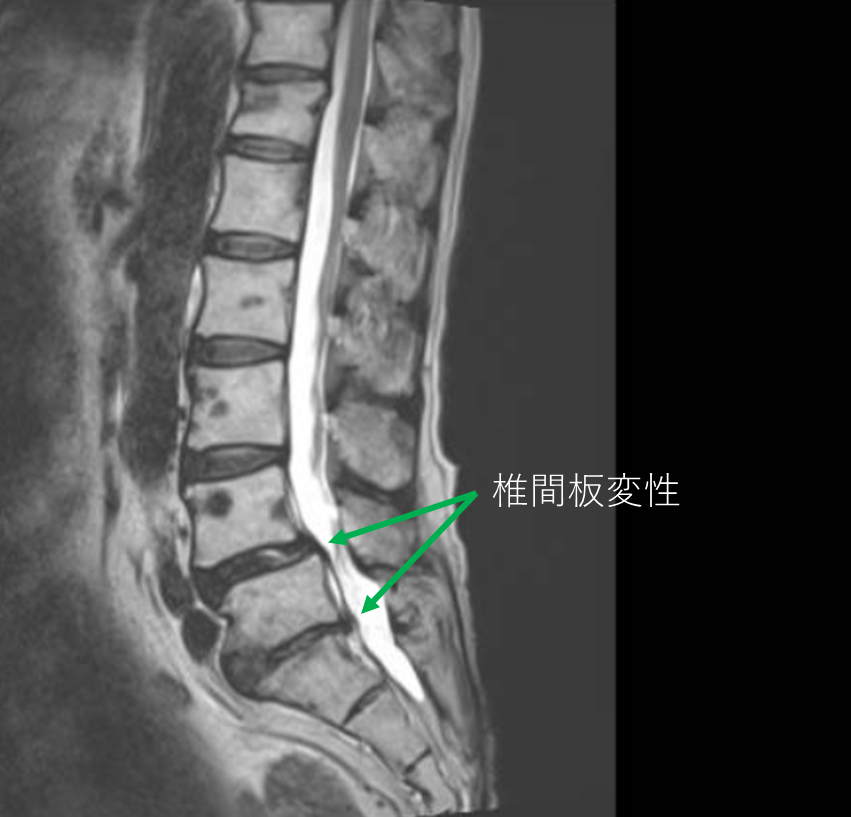

画像及び所見について

- L4/5,5/s-椎間板変性

- L4-前方滑り

以上の事が画像上認められます。

・L4/5,5/s-椎間板変性を認め、主症状の原因の可能性が高い